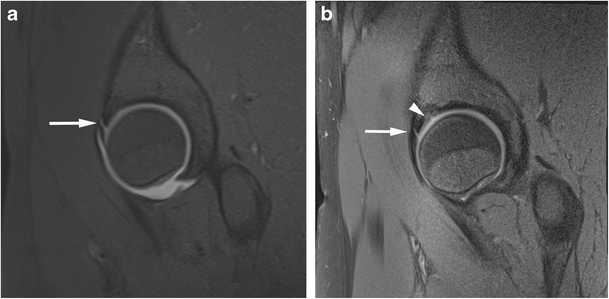

Acetabular labrum complete tear in a 27-year-old confirmed at surgery. Sagittal (a) T1 FS 1.5T MRA and (b) PD FS 3T MR images show complete basal labral tear (arrow) and normal articular cartilage (arrowhead)

Acetabular labrum complete tear in a 29-year-old confirmed at surgery. Sagittal (a) T1 FS 1.5T MRA shows no tear (arrowhead) and (b) PD FS 3T MR images shows complete basal labral tear (arrow)

Anterosuperior acetabular labrum partial tear with adjacent cartilage delamination in a 28-year-old confirmed at surgery. Coronal (a) T1 FS 1.5T MRA image shows partial labral tear (arrow) and the adjacent cartilage shows increased linear basal fluid signal (arrowhead). (b) PD FS 3T MR image shows partial labral tear (arrow) and the adjacent cartilage shows low chondral signal (arrowhead) indicating delamination